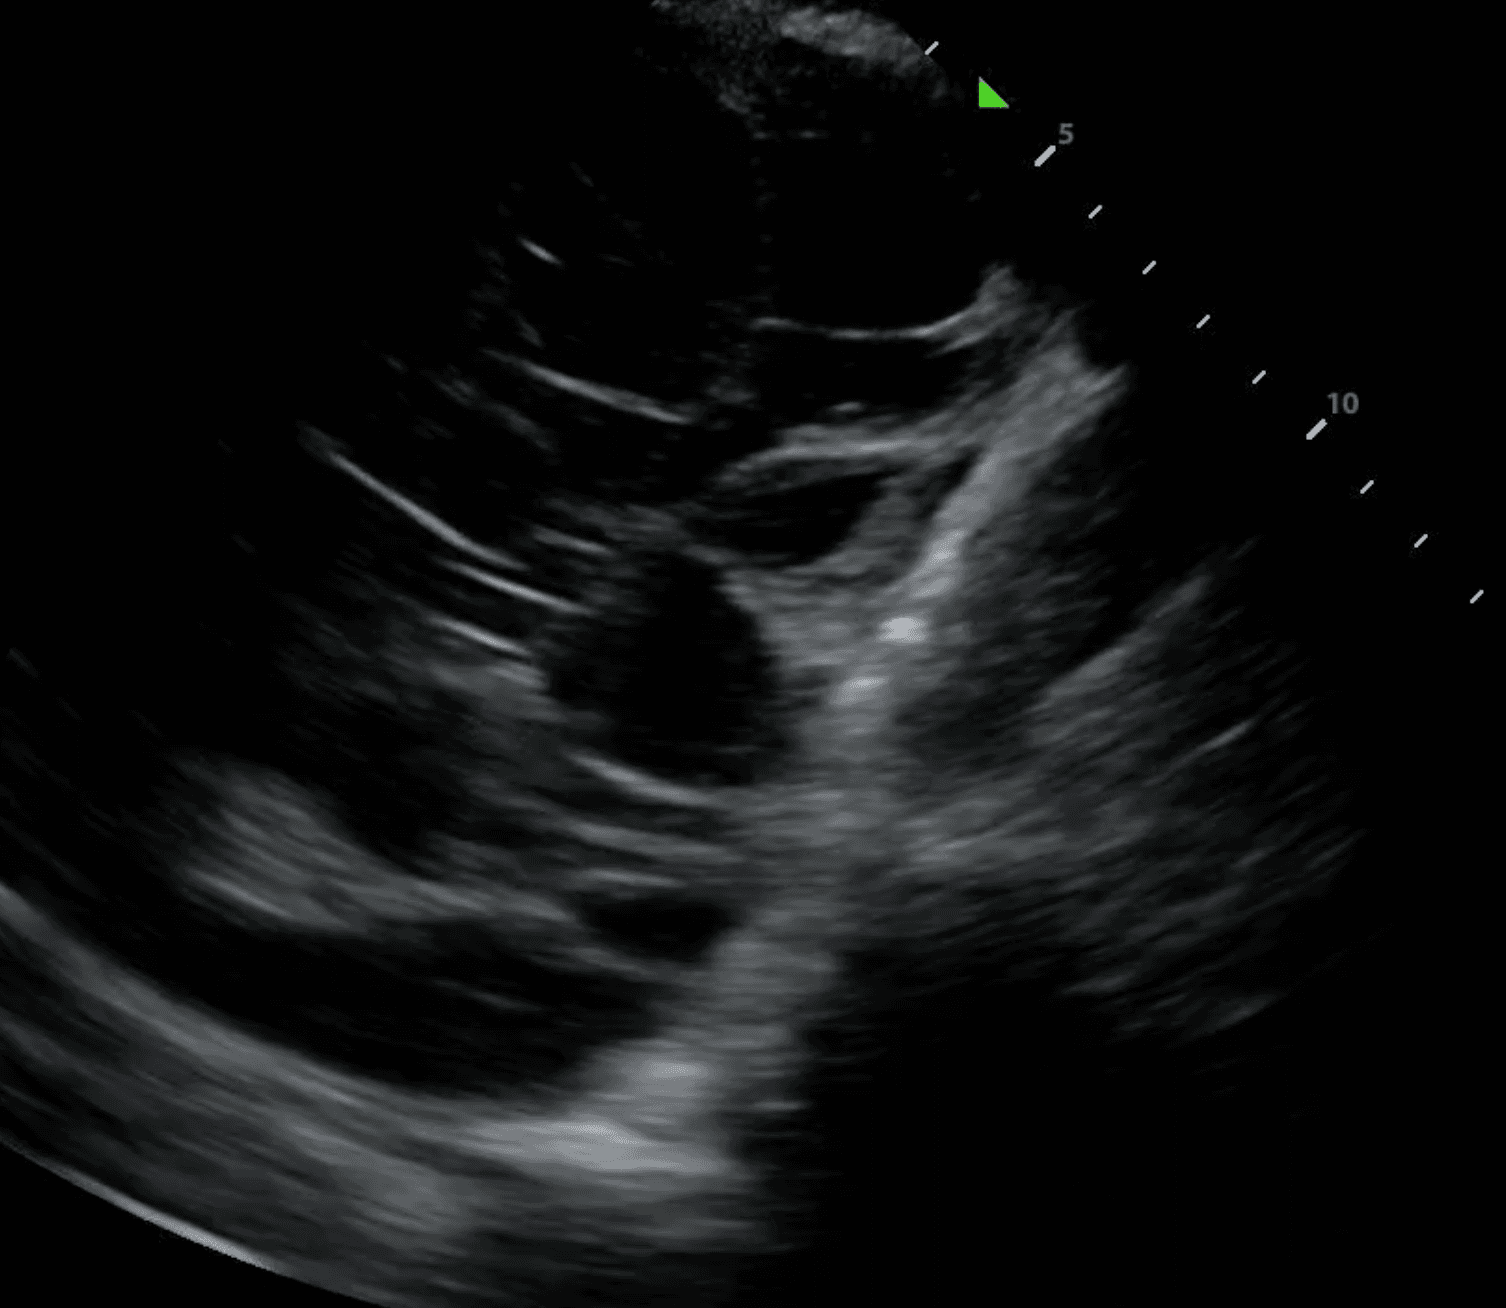

A subpleural consolidation refers to a consolidation underneath the pleural line. While all lung consolidations are technically subpleural, consolidations that extend through the entire lung are referred to as translobar. Compared to translobar consolidations, subpleural consolidations are smaller, tend to occur in the anterior lung and normal tissue can generally be viewed beneath the lesion. They tend to reflect an inflammatory cause, such as pneumonia, infarction from pulmonary embolism and metastatic lesions.

The shred sign, also known as a fractal sign, describes the border between abnormal and normal lung. It separates a subpleural consolidation from underlying normal lung. It has been described as “torn paper” as its irregular boundary contains jagged segments. Visualization of the shred sign helps localize focal consolidations that are likely to be missed on chest X-ray. This allows for early intervention to treat conditions such as pneumonia before they progress.